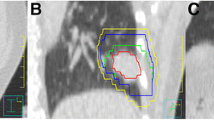

CBCT image-guidance correction protocol

The absolute tumor prediction errors \( \left| {{{\bar{e}}}_{x/y/z}} \right| \) were summarized for all selected fractions across all individuals and over each individual in Fig. 2. \( \left| {\bar{e}} \right| \) ≥ 5 mm occurred in 12.5 % of the patients in the CC direction, while \( \left| {\bar{e}} \right| \) ≥ 3 mm was found in 19 % of the patients in the LR, 31 % in the CC, and 0 % in the AP directions. For all fractions, maximum \( \left| {{{\bar{e}}}_{x/y/z}} \right| \) were 7.6/11.1/6.4 mm. A larger lipiodol-to-diaphragm distance D in the planning 4D-CT scan was associated with a larger \( \left| {{{\bar{e}}}_{x/y}} \right| \)(p < 0.05) but not \( \left| {{{\bar{e}}}_{z}} \right| \) (p = 0.23; Fig. 3). Two patients who showed \( \left| {{{\bar{e}}}_{y}} \right| \) > 5 mm had D > 6 cm. Except for the AP direction in which the correlation between \( \left| {{{\bar{e}}}_{z}} \right| \) and motion range was marginally significant (p = 0.058), the tumor prediction errors \( \left| {{{\bar{e}}}_{x/y}} \right| \) were statistically independent of the LR and CC motion ranges (p > 0.05). The 4D registration results obtained with the lipiodol and diaphragm masks are shown in Fig. 4. When registration was made according to the diaphragm, noticeable target misalignment was observed, compared with the lipiodol reference.

Planning contour of the gross tumor volume (GTV) overlaid on the time-weighted average 4D-CBCT images after registration using lipiodol (top row) and the diaphragm (bottom row). Misalignment of the GTV was observed when target localization was made using the diaphragm as a surrogate, as indicated by the arrows